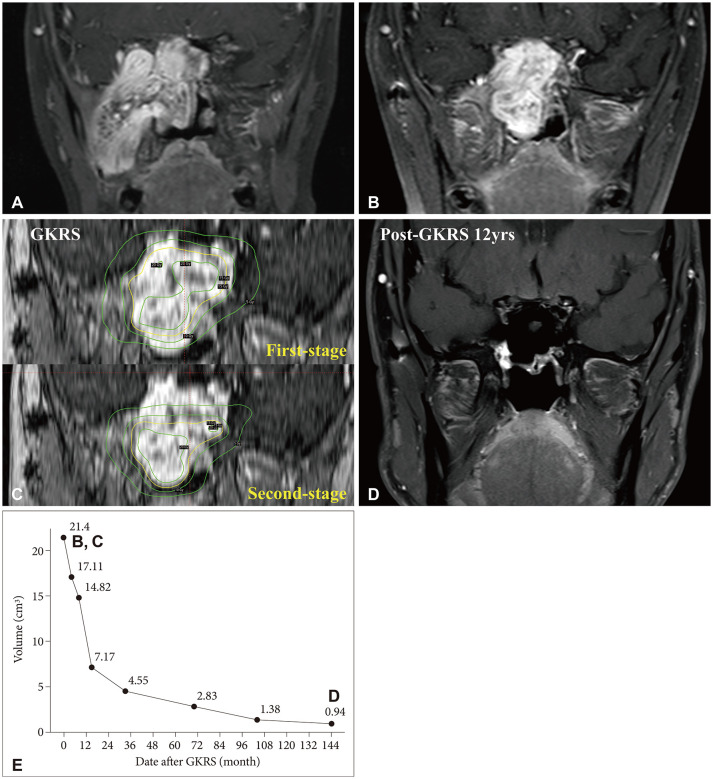

Juvenile nasopharyngeal angiofibroma (JNA) is a rare, benign, but locally aggressive tumor that typically affects adolescent males. While surgical resection is the standard treatment, achieving total resection is often challenging in advanced-stage tumors with intracranial extension, resulting in high recurrence rates. Gamma knife radiosurgery (GKRS) has been suggested as a potential adjuvant or salvage therapy, but evidence remains limited. In this study, we report three pediatric cases of advanced-stage JNA treated with GKRS following incomplete surgical resection. Two patients demonstrated durable local tumor control with a significant reduction in tumor size until 2 and 12 years after GKRS. The other patient with partial coverage of tumor by prescription isodose 12 Gy showed a reduction of tumor volume at 6 months but subsequent progression at 1 year. No GKRS-related complications were observed during the follow-up period. Our findings suggest that GKRS appears to be a potentially safe and effective treatment modality for residual or recurrent JNAs. Fractionated or staged GKRS combined with surgery may be a preferable strategy for large tumors in which extensive surgery alone, conventional radiotherapy, or single-fraction radiosurgery may be associated with increased morbidity in pediatric populations.